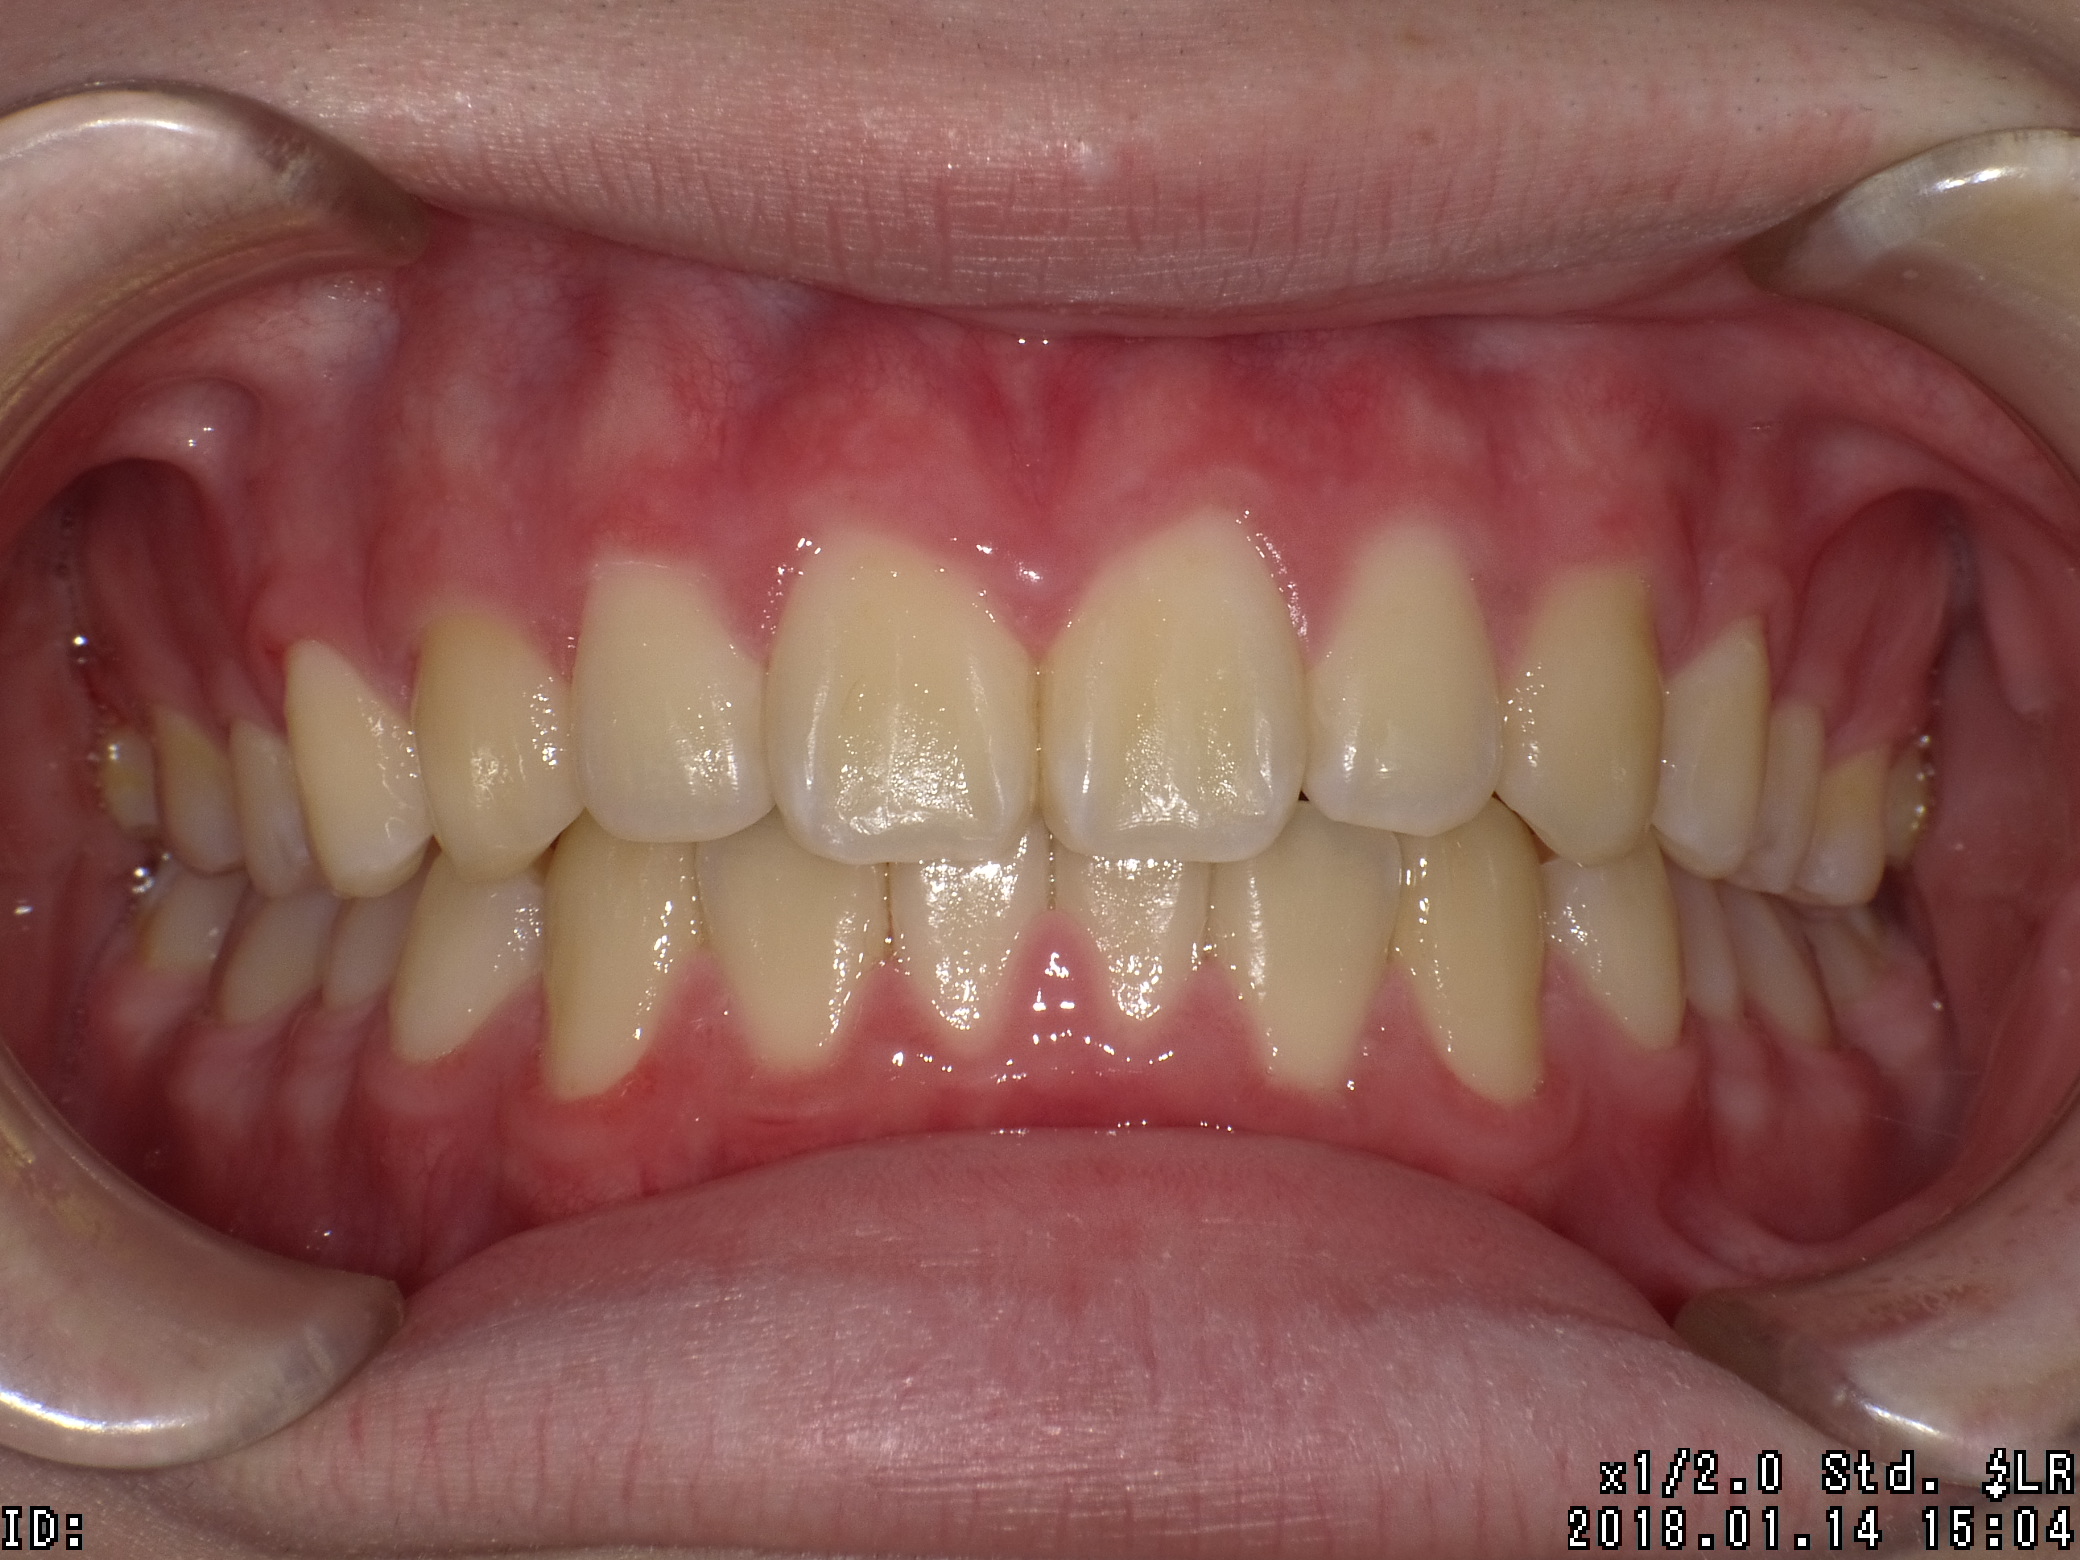

| 治療期間 | 2017年04月 〜2019年08月 |

|---|---|

| 治療費用 | 約700,000円 |

| 抜歯有無 | 抜歯有り |

| 矯正箇所 | 上顎・下顎 |

| 治療のリスク | 治療の過程で使用する針金やゴムにより、違和感や不快感を感じたり、口内炎になることがあります。 |